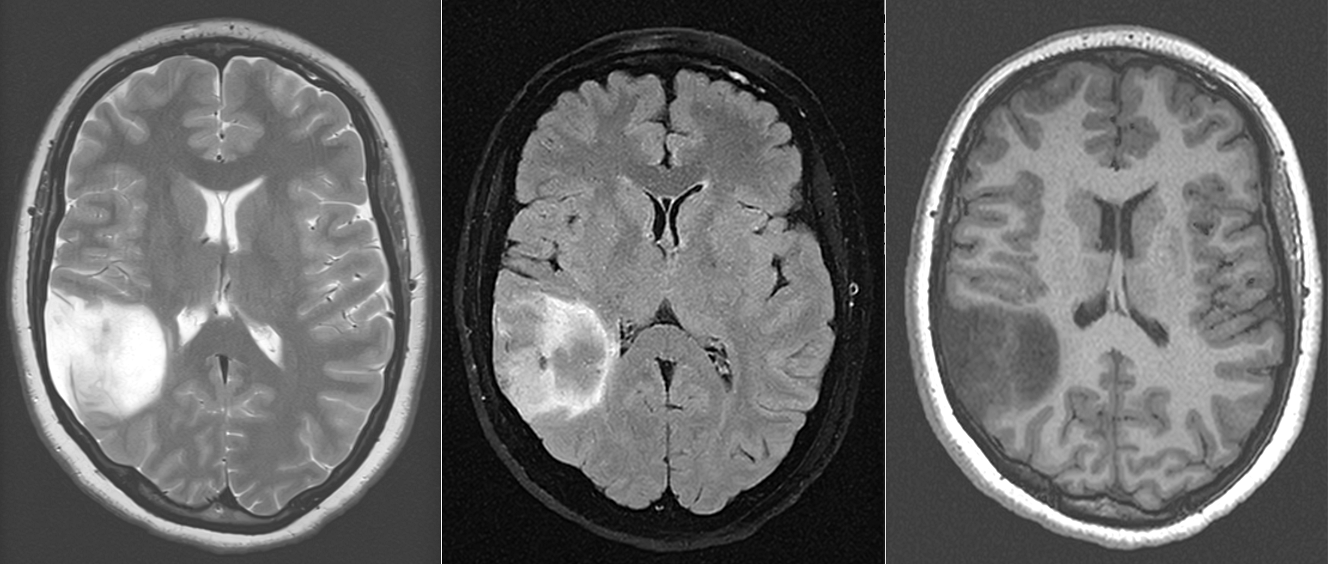

b) Rezonanța magnetică nucleară (IRM / RMN)

- Este investigația imagistică de elecție în diagnosticul tumorilor cerebrale.

- Permite o vizualizare detaliată a creierului și a relațiilor dintre tumoră și structurile învecinate.

- Se efectuează în mai multe secvențe (T1, T2, FLAIR, DWI, perfuzie, spectroscopie etc.).

- Administrarea de gadoliniu (substanță de contrast) ajută la evidențierea vascularizației tumorii și la diferențierea între leziuni benigne și maligne.

d) RMN de difuzie și perfuzie

- Analizează fluxul sanguin tumoral și gradul de celularitate.

- Sunt utile în diferențierea între tumori de grad înalt și cele de grad scăzut.